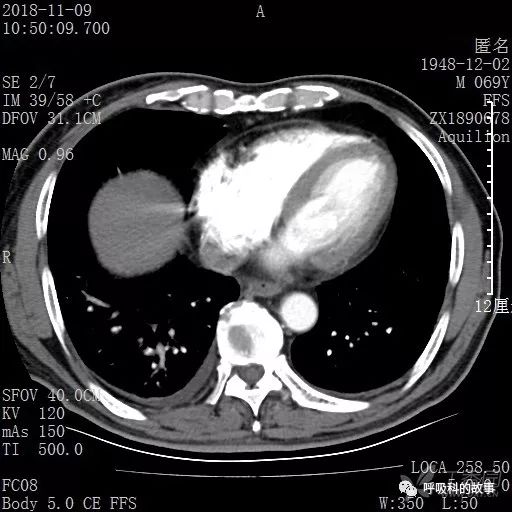

胸部增强CT示右肺门占位伴远端阻塞性肺炎,纵膈、右肺门、右侧颈根部、右侧腋下及肝门部肿大淋巴结。两侧胸腔少量积液。

纵隔窗的增强CT

肺窗CT